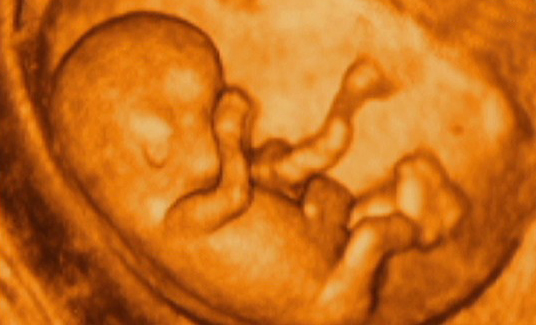

为宝宝留下成长的足迹是每一个准爸妈都想做的事情,准爸妈总是好奇宝宝在肚子里的动态,为了满足准爸妈的好奇心,安徽安琪儿妇产医院引进美国GE—E8四维彩超技术,该技术是目前国际上最先进的四维彩超技术,高清动态的显示胎儿的身体、骨骼、器官的发育情况,并通过高科技技术将宝宝的四维彩超影像刻成光盘,真正的实现零岁动态写真,可供准爸妈随时、反复的观看,为宝宝留下最珍贵的时刻。

四维彩超是目前最先进的一种彩超技术,准妈妈可以清楚的观看到宝宝的动态图像。医生也能够根据四维彩超图了解宝宝的发育情况,是否有唇裂、脑积水、畸形等异常情况,方便医生和孕妇及早的采取应对措施;根据胎儿现今的发育情况及时补充营养,更有助于宝宝的身体发育和智力发育,提高宝宝的健康指数。